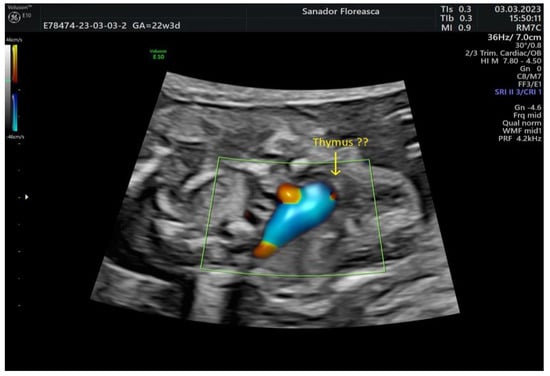

| Gestational age at cardiologic diagnosis | 22 weeks |

| Cardiologic diagnosis | IAA type B, malalignment-type VSD, pulmonary valve dyplasia, ARSA |

| Other ultrasonographic findings | Polyhydramnios Enlarged CSP Thymus hypoplasia Bulbous nose |